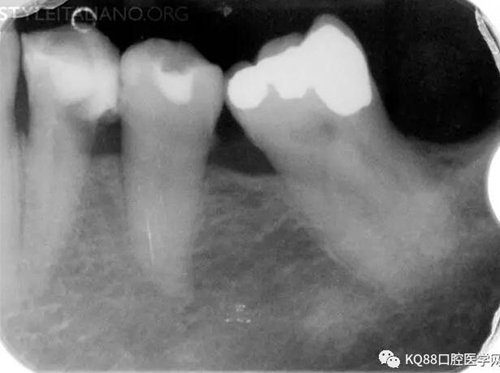

Img. 3 - The frequency of post-endodontic pain is higher in teeth with periapical or periradicular lesions. Infected debris can be forced in the periradicular tissue through a resorpted apex, thus generating acute inflammation. Creating a glide path prior to instrumentation and using a step-down technique can reduce the amount of extruded debris.

Img. 4 - Case 2: This necrotic first mandibular molar was treated in one visit, and the patient complained of post-operative pain. Analgesics and antibiotics were prescribed, and occlusion relieved. Symptoms disappeared after two days, and a radiographic follow-up after two years showed healing of the periradicular lesion.